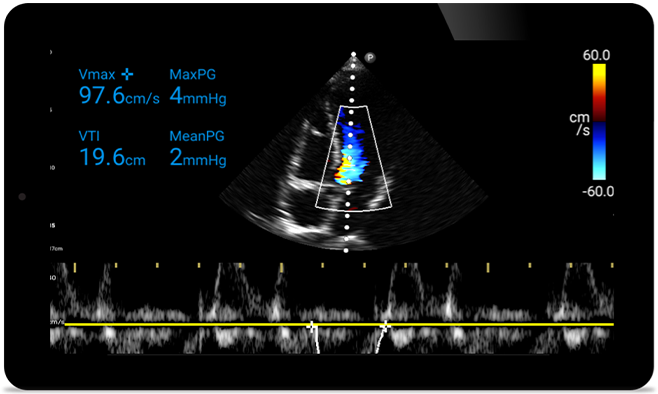

Act faster to protect their heart

When seconds count, portable ultrasound can make the difference. Lumify can provide the high-definition imagery you need whenever and wherever you need it.